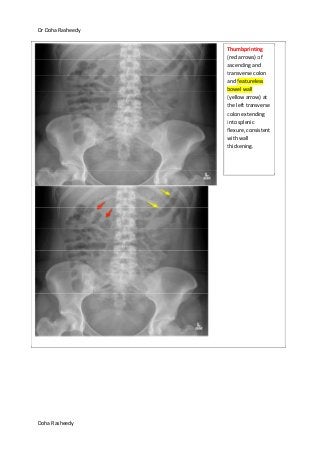

Thumbprinting

(red arrows) of

ascending and

transverse colon

and featureless

bowel wall

(yellow arrow) at

the left transverse

colon extending

into splenic

flexure, consistent

with wall

thickening.